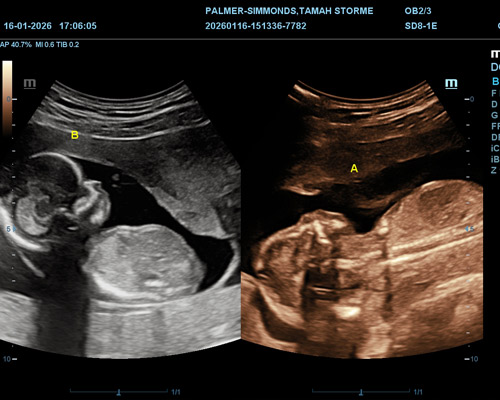

- Complimentary 4D preview (optional)*

Ultrasound technology used for twin scans is safe and non-invasive. It works using sound waves to create images and does not involve radiation.

All scans are performed by trained professionals who follow recognised guidelines. Modern equipment is used to ensure clear and accurate imaging for both babies.

Our goal is to provide a twin pregnancy scan near Wakefield that is safe, reliable, and carried out with care and attention.